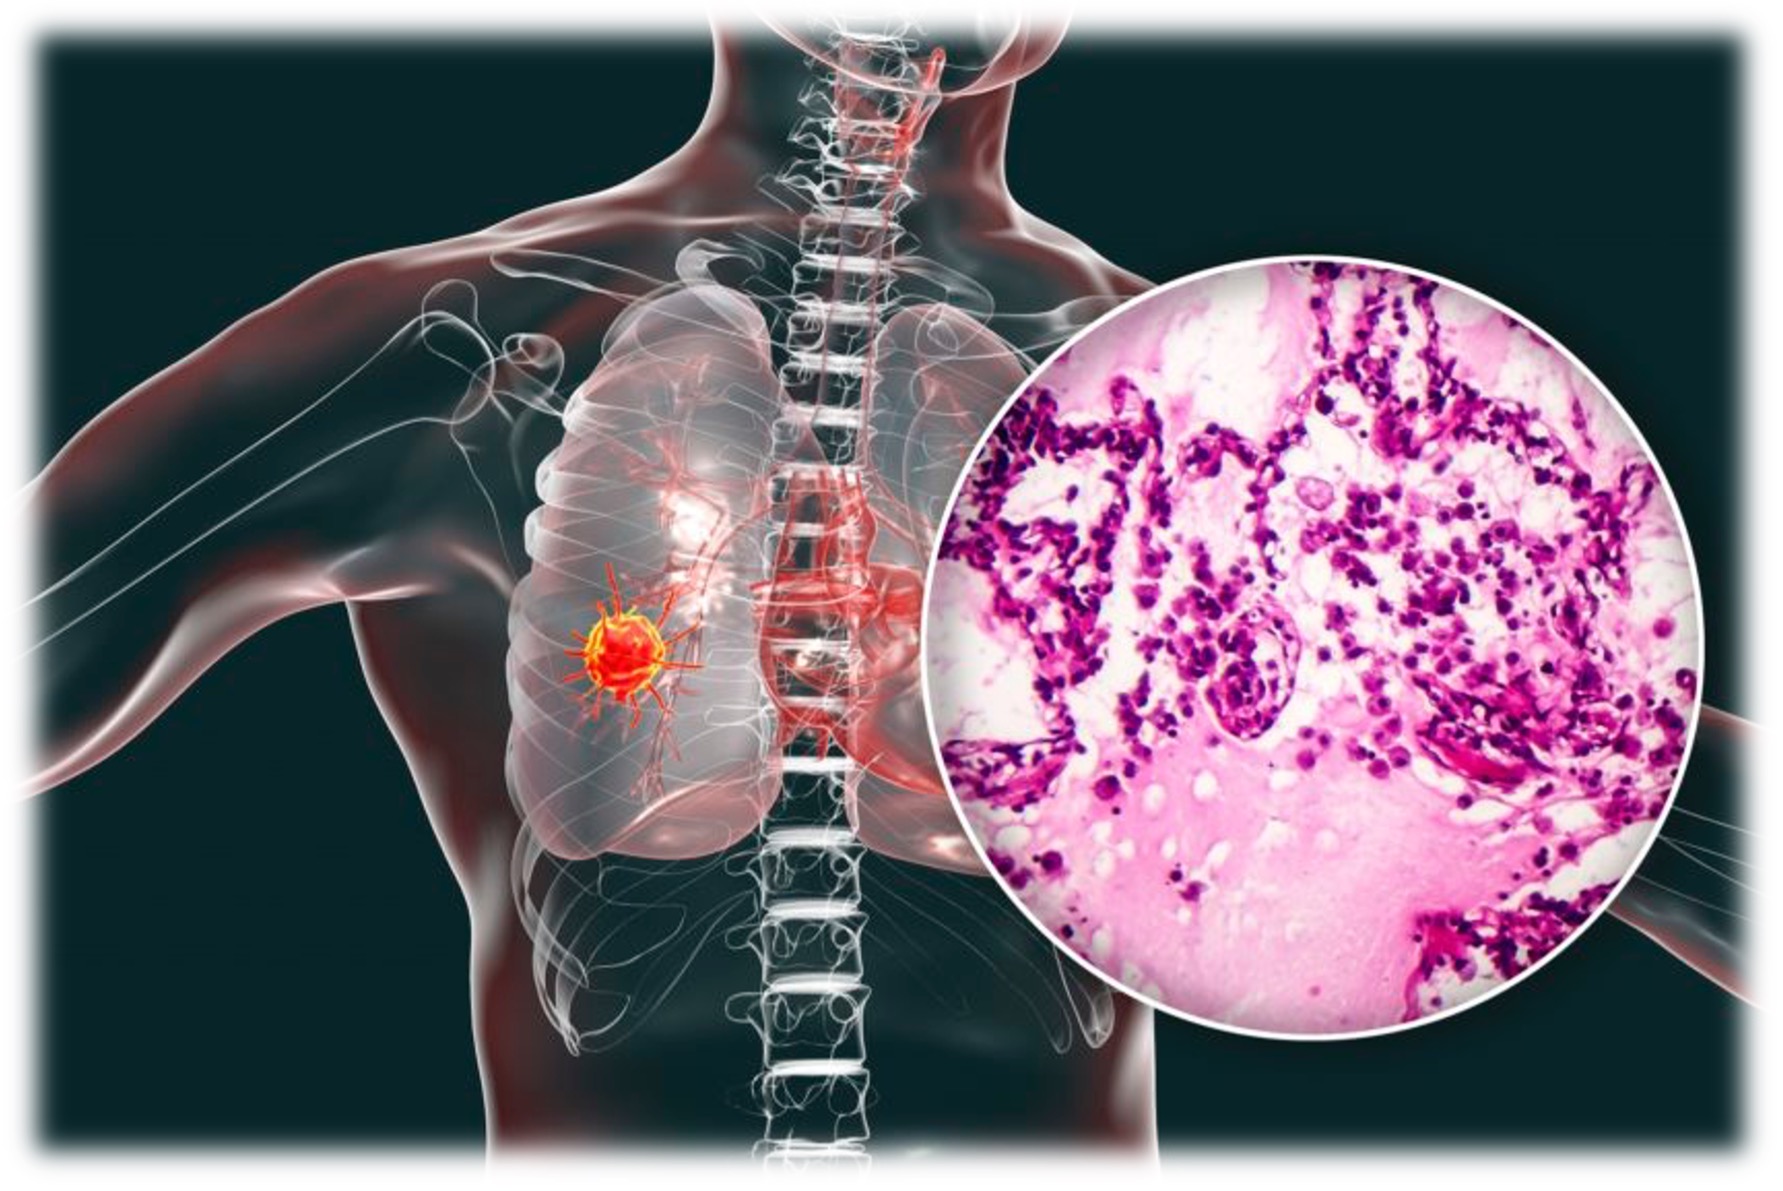

۲. سرطان ریه

سرطان ریه بیشتر در افراد سیگاری و کسانی که در معرض آلودگی هوا یا مواد شیمیایی هستند شایع است.

علائم اولیه:

- سرفه مداوم یا بدتر شدن سرفههای مزمن.

- خون در خلط یا سرفه خونی.

- تنگی نفس یا احساس خفگی هنگام فعالیتهای روزانه.

- درد قفسه سینه یا شانهها.

- خستگی غیرعادی و کاهش وزن بدون دلیل.

نکات کاربردی:

- افراد پرخطر باید آزمایش تصویربرداری (مثل سیتی اسکن کمدوز) را بررسی کنند.

- سرفه طولانی بیش از دو هفته را جدی بگیرید.